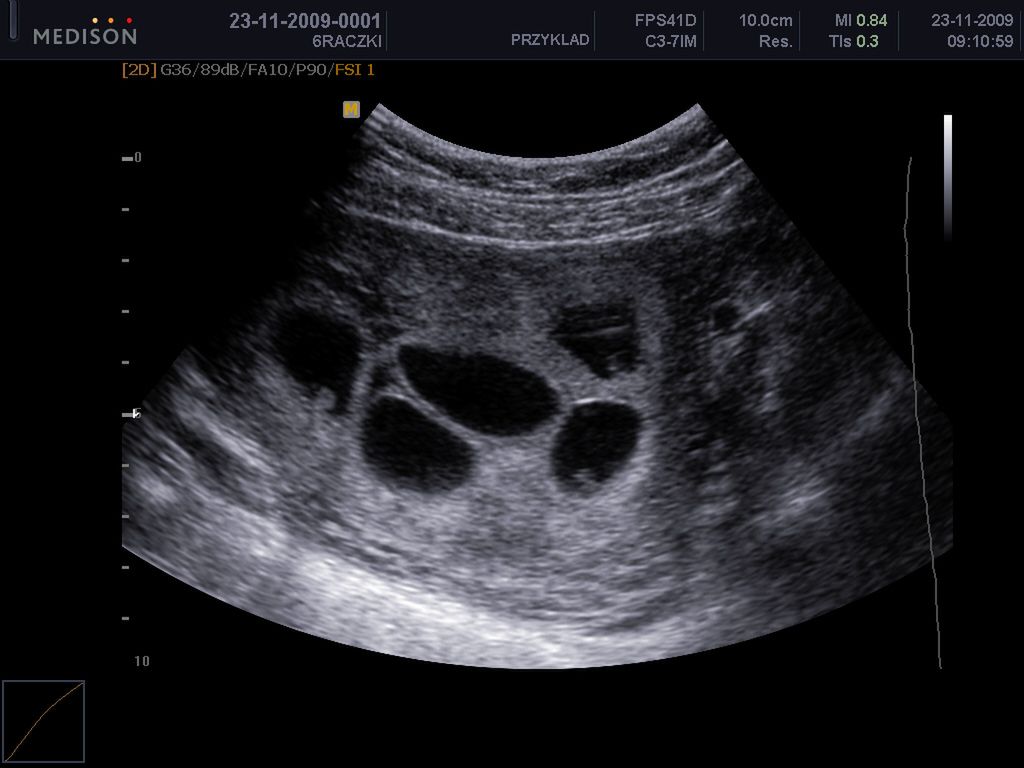

Płód w 6 tygodniu ciąży

Dziecko w 6 tygodniu ciąży ma kompletny układ nerwowy, dynamicznie rozwija się wątroba

/ 1Płód w 6 tygodniu ciąży - obraz USG